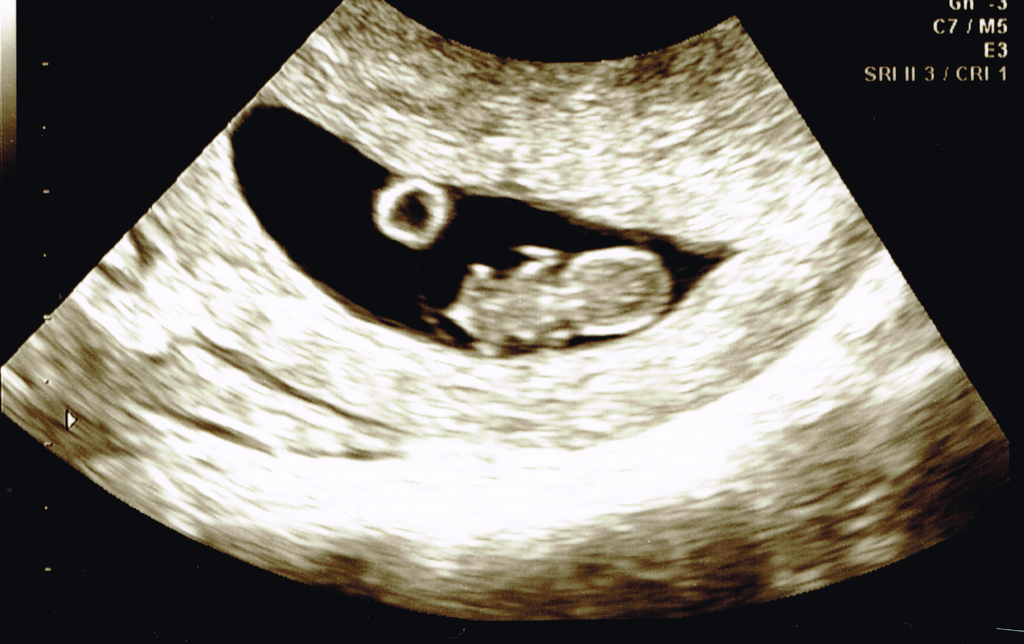

• US is scheduled a week from today, Im super ready to see proof of this little sweetie who's causing my daily nausea (tamed by wheat thins, btw)!

A first pregnancy making it past 6weeks (I miscarried once at just over 5 weeks) at my ridiculous age 37--I definitely feel nervous. Many of you are seasoned mommies-to-be at a decade younger! Words of wisdom from you all has really helped me these past few weeks, thank you :)

BFP 6/26/15 - EDD 2/26/16